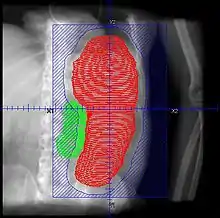

- Patients should be continuously monitored, and fields adjusted with shrinking spleen

- Retrospective. 22 courses for 19 patients. Total dose 1.5 - 8.0 Gy (median 4.5 Gy), fractional dose 0.25 - 1 Gy delivered weekly or twice weekly. AP/PA. Median field reduction 25%

- Retrospective. 22 patients with 32 courses of SI. RT 0.25 - 0.5 Gy/fx, fields AP/PA and decreased with response, treatment halted with response